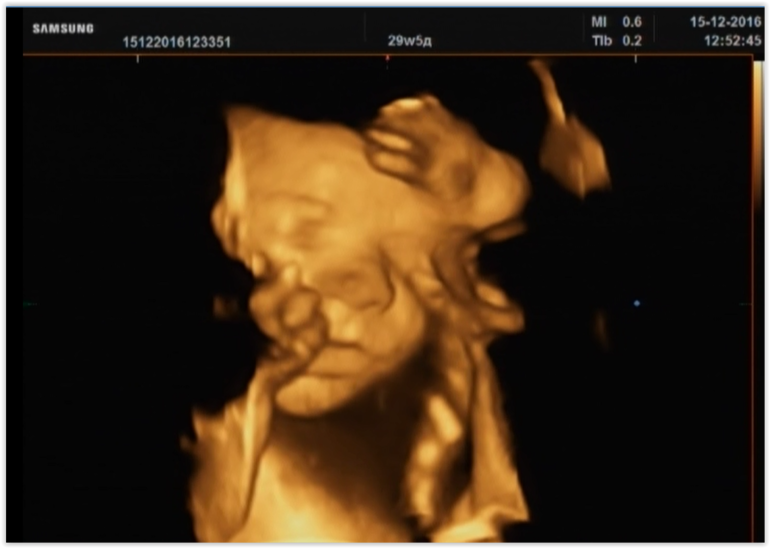

09.11.2016 25 недель

Сходила в АРТ-МЕД на экспертное узи, как и с Даником. Любимую Мазырко выловить не удалось, ушла с последнего места работы и никаких данных-контактов найти не удалось( Пошла к Затикян по совету ББшек. Отточенными профессиональными движениями она быстро все измерила, проверила, показала мне несколько неплохих 3D, но стоило только включить на запись - моя красавица отвернулась к миру жопой и стала злобно бить меня внутрь ногами. На конфетку не поддалась. Ну что ж, теперь только в 32 недели еще раз попробуем. Но надежды мало, ибо характер.

Эмилия здорова, 32 см и 903 гр весом. Она, по словам профессора, 100% девочка и у нее точно ничего уже не отрастет между ног.

Все развивается хорошо, в норме, вопреки моим страхам кровоток всех органов и матки отличный, плацента отличная, ребенок упитанный, активный и изголодавшимся не выглядит. Это главное! 6 тыщ за это конечно жалко, но что делать. Скоро надо на учет вставать... охххххх....